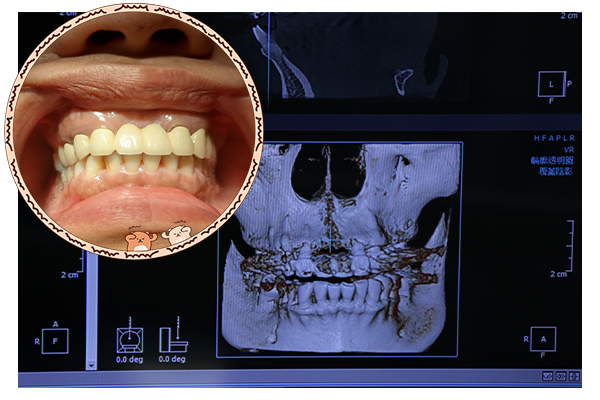

曾有植牙案例年齡57歲男性植牙才做3年就搖搖欲墜,由於病人本身有牙周病的狀況,植牙術後口腔衛生習慣不佳,才導致植體已經搖晃,到新全美牙醫院內求診後,檢查結果發現是「植體周圍炎」

「植體周圍炎」就是植牙的牙周病,產生的原因與牙周病一樣也是清潔不良所造成,使得細菌感染而造成植體周圍組織發炎,導致牙齦和支持的骨頭喪失。

美國牙周病學會研究報告指出,有90%的植體周圍炎,是因為原本病人存在的牙周病未被治療及控制所引起。其他例如咬合力過重、創傷性咬合而造成傷害、不當的贋復設計、殘留的黏著劑等也會造成植體周圍炎。